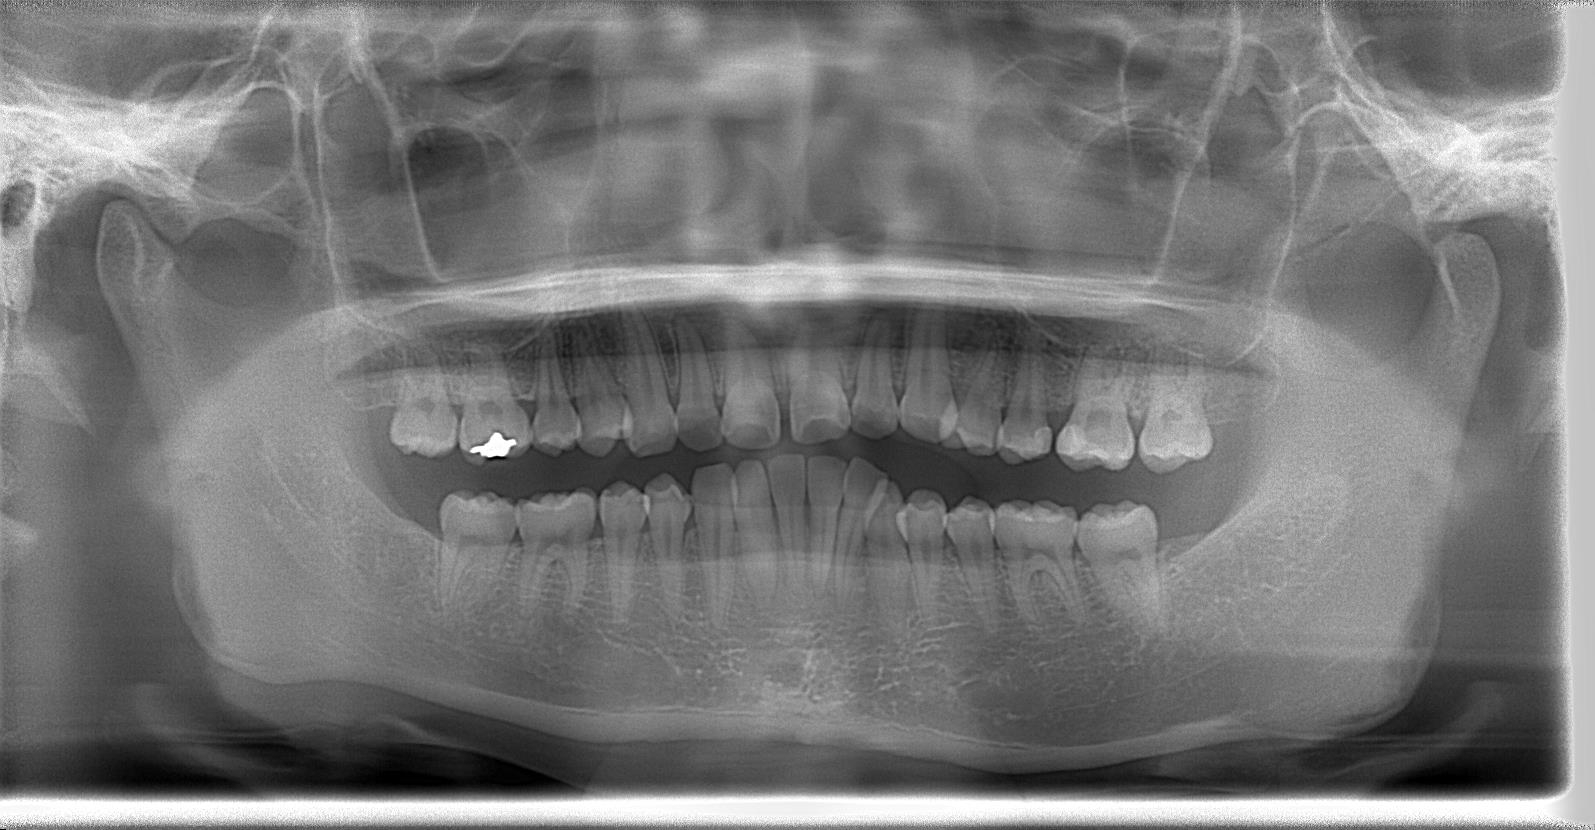

[術前パノラマレントゲン写真]

第3大臼歯を抜歯して矯正配列している症例です。